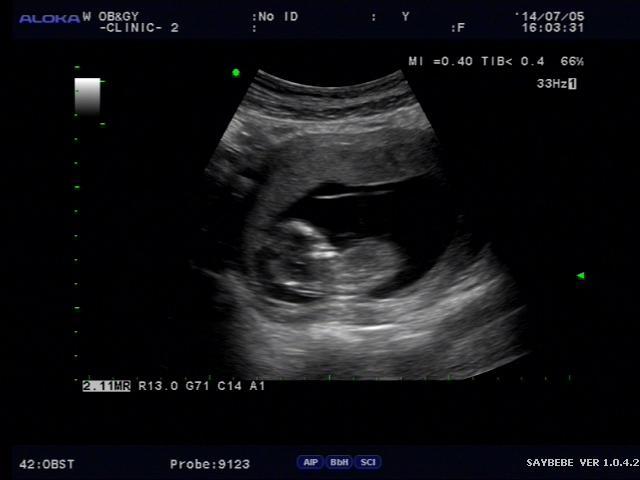

병원은 어지간하면 같이 가주는 것이 좋다. 혼자 있는 여자는 나도 많이 봤지만 참 안스럽다. 초음파나 그런 것을 할 때도 함께 하는 것이 더 극적이고 더 기쁘다. 물론 회사일 때문에 매번 같이 가주는게 어렵지만 요즘 병원은 토요일도 여니까 주 5일 근로자라면 같이 가주자.

2014-07-12 12.12.52.jpg 우리 도윤이 꼬물이 시절